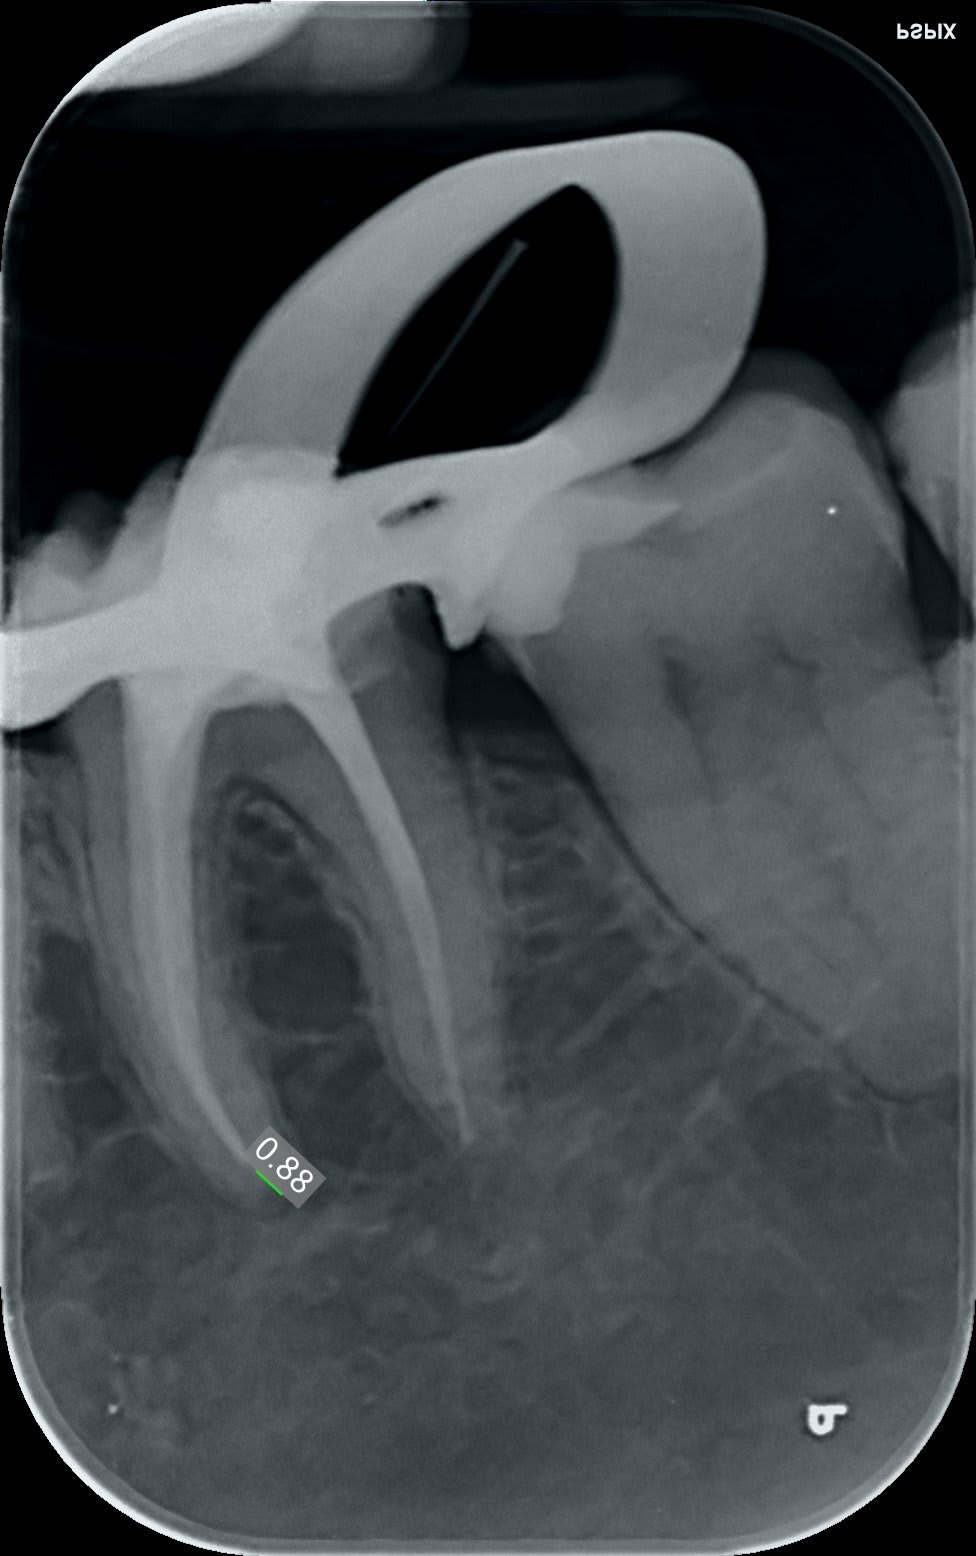

Fatalitas !!!!

Au premier passage et avec la fonction anat de sélectionnée ☹️

et puis finalement, limes k... protapers golds... R25 blue... US...

cones en place c'est acceptable, c'est bien d'avoir du temps et du matos.

Endo 36 1 dy2wul - Eugenol

C'est bien d'avoir mis la digue aussi...

c'est pas l'endo du siècle, mais le canal (les ..?) latéraux en distal y sont, le localisateur d'apex les avait bipé et en mésial on est pas si mal, c'est la qualité de la radio qui est trompeuse... il faut que je recalibre les expositions.

0.88 c'est la mesure la plus défavorable, la plus favorable donnait 0.15 par rapport à l'apex radiologique et le réciproc donnait toutes les barres avant apex.

Endo 36 2 lcspc4 - Eugenol